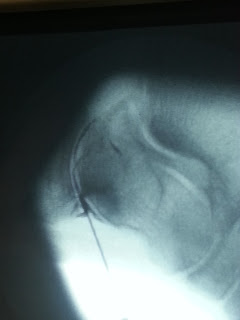

Letzte Woche war ich zu einer Voruntersuchung dort - vier Stunden mit Kontrastmittel im Blut - der Fuß wurde mehrfach geknipst. Geknipst ist ja eigentlich nicht richtig - geröntgt aber auch nicht, also er wurde halt wie in einem MRT durchleuchtet um zu sehen ob die Artrose (die mir durch den Unfall die Probleme macht) weit fortgeschritten ist. *Weichteilszintigraphie

Nachdem er mich zurechtgeruckt hat, gab´s dann auch den ersten Stich und der erste Stich sollte auch der letzte sein. Durch die Nadel wurde erst was abgezogen und dann ZACK Betäubung rein, ZACK Kontrast rein, ZACK Rhenium-186 rein. Pflaster drauf. Fertig. Keine 5 Minuten. Ich kann nicht sagen, das ich nichts bemerkt habe aber es ist schon auszuhalten.

Während ich noch fasziniert auf dem Bildschirm geguckt habe, stand der Dr. schon auf und schüttelt meine Hand.

Die netten Sprechstundenhilfe haben mich dann in den nächsten Raum geschoben, wo eine erneute Aufnahme (Verteilungzintigrafie) gemacht wurde.

Da die Hilfen so nett sind, hat mein Bloggerherz nochmal Mut gefasst und sich getraut nachzufragen ob ich vielleicht ein Bild von meinem Gelenk mit Spritze haben kann. Die finden das total witzig und plötzlich kommt der Dr. nochmal rein und zeigt mir tatsächlich nochmal mein Gelenk und weil ich noch nicht geschient bin und weit von der Lichttafel weg bin, nimmt er mein Handy aus der Hand und knipst tatsächlich das Bild selber.